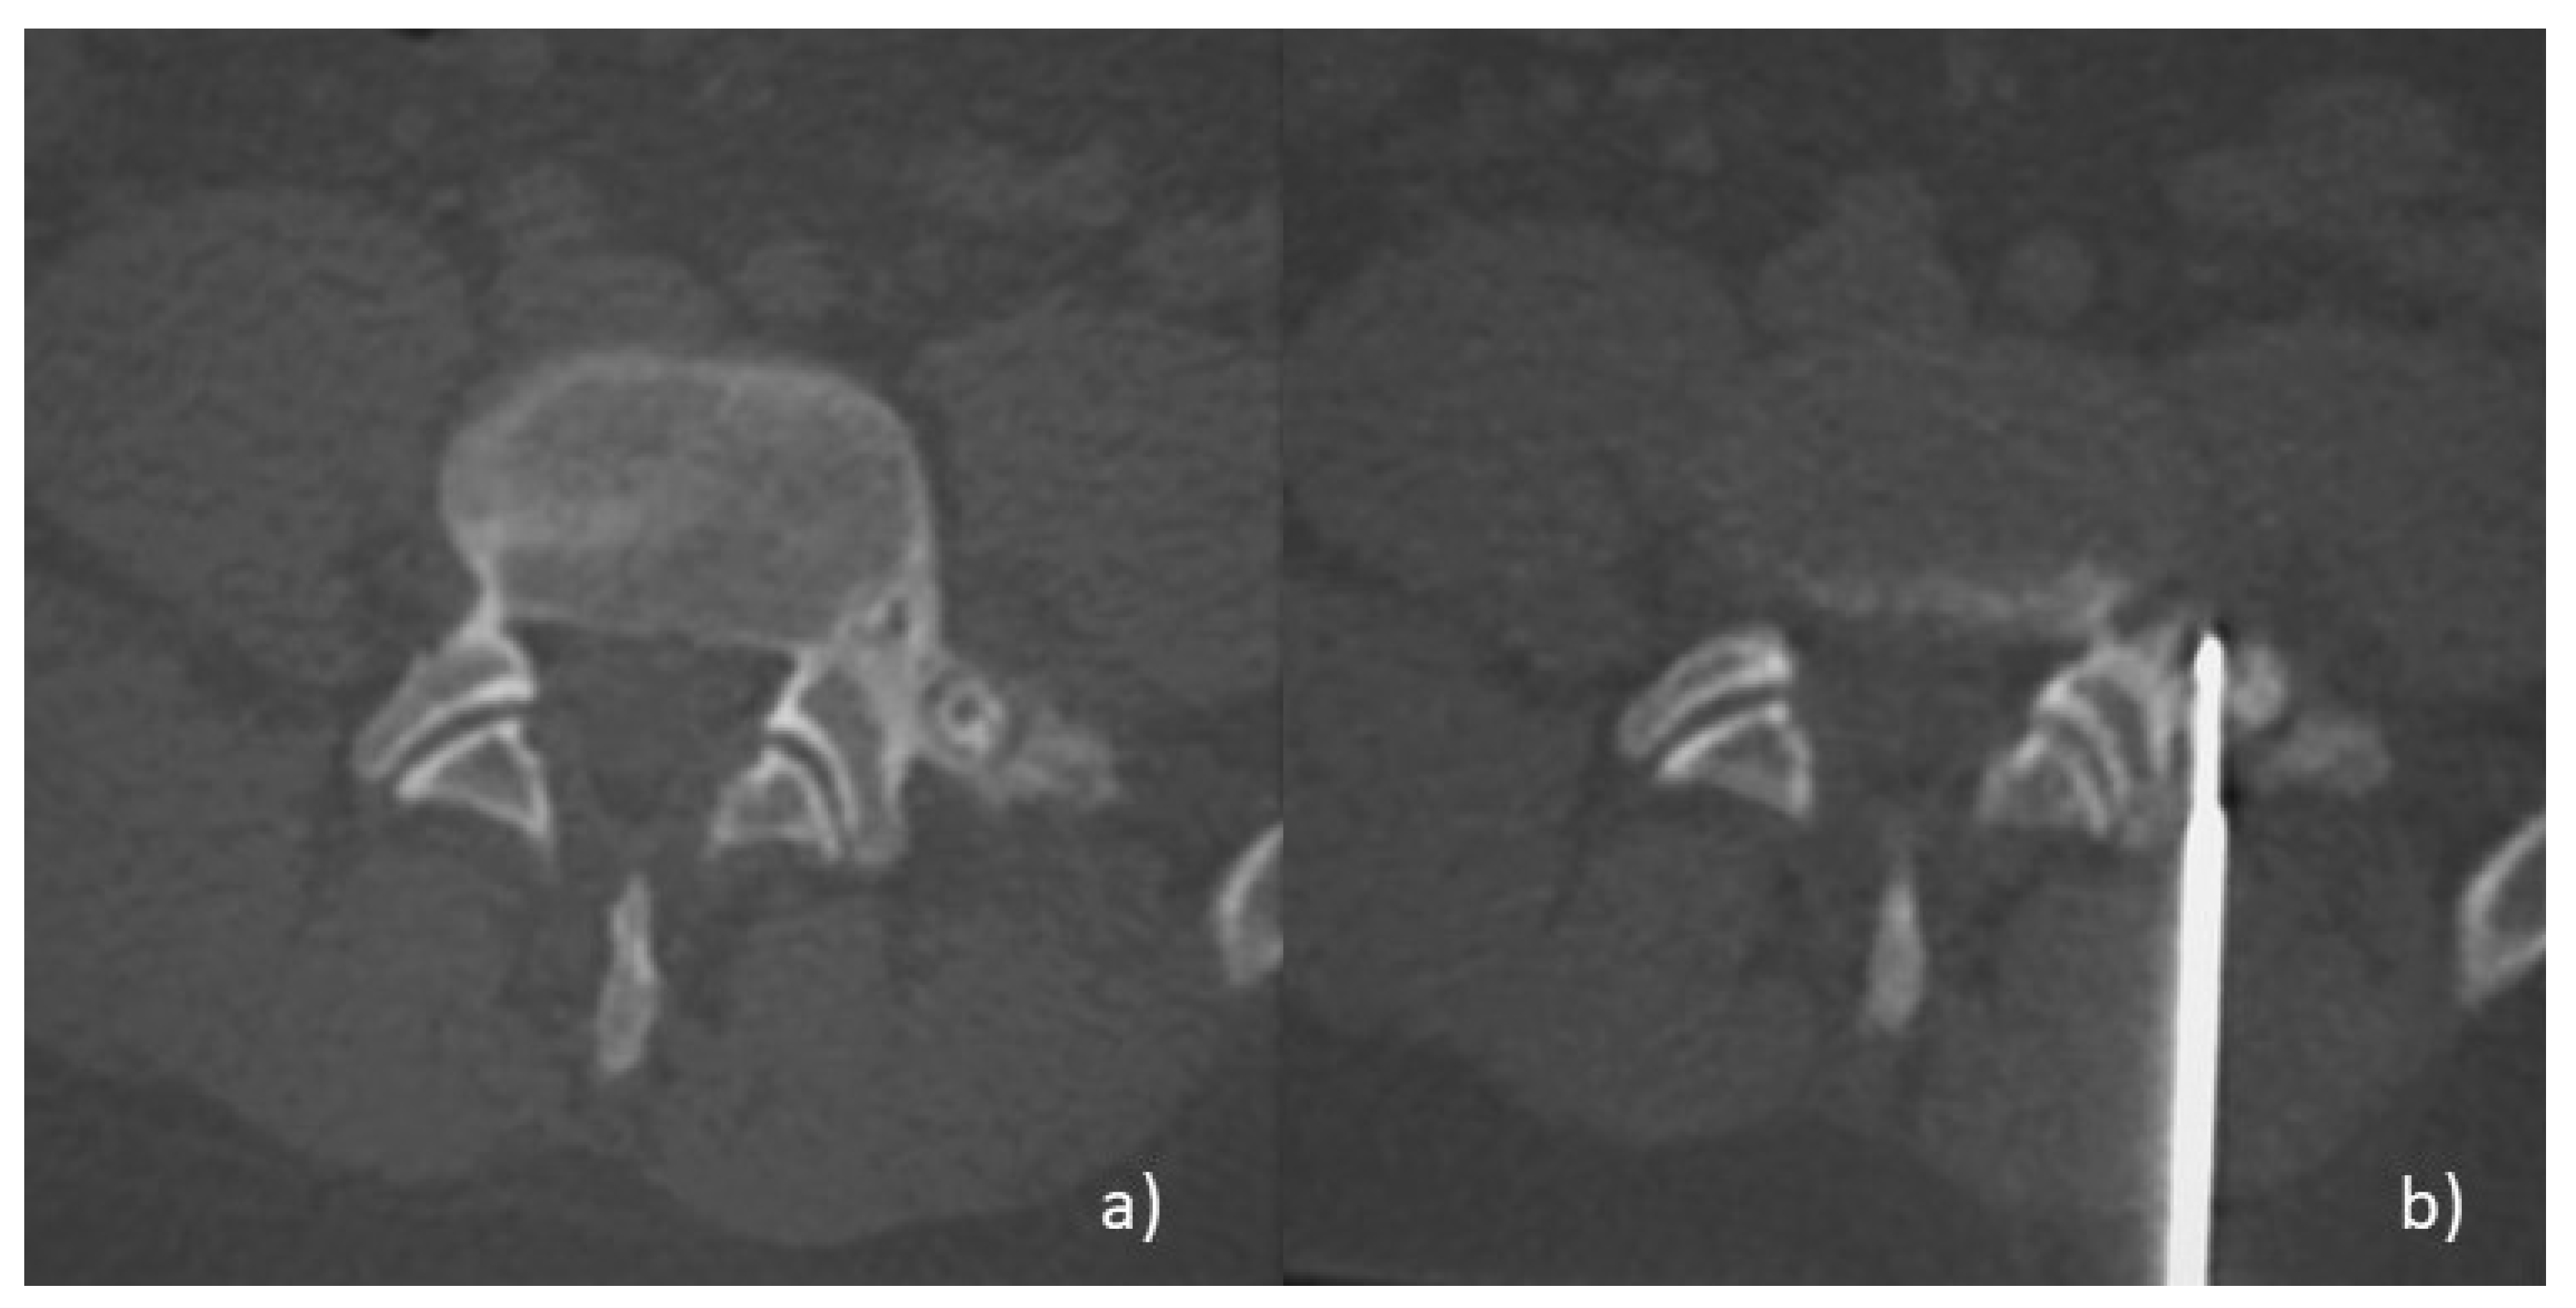

- Arrigoni, F.; Barile, A.; Zugaro, L.; Fascetti, E.; Zappia, M.; Brunese, L.; Masciocchi, C. CT-guided radiofrequency ablation of spinal osteoblastoma: Treatment and long-term follow-up. Int. J. Hyperth. 2018, 34, 321–327. [Google Scholar] [CrossRef] [PubMed] [Green Version]